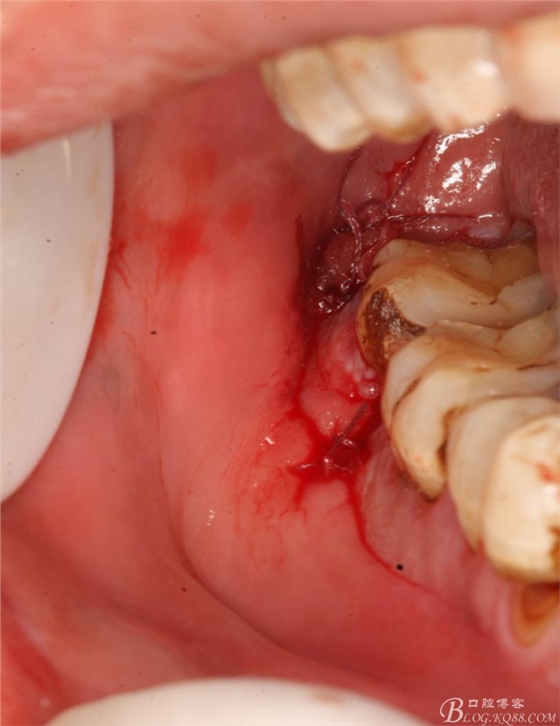

48未萌出,47遠(yuǎn)中可探及深約7mm的牙周袋。頰側(cè)47、48之間牙齦紅腫,有少量血性滲出。X線根尖片顯示:48牙冠反轉(zhuǎn)倒置,47遠(yuǎn)中牙槽骨吸收明顯。CBCT顯示:48牙冠近中面位于下頜管內(nèi)。

2.切開(kāi)翻瓣

3.去骨、暴露48.